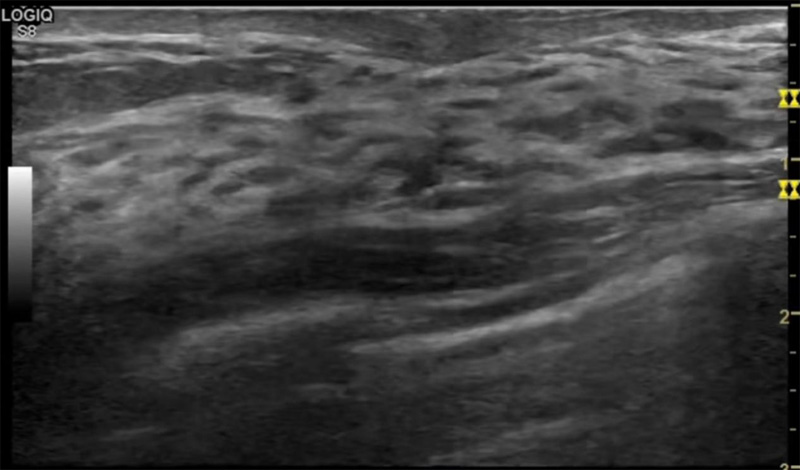

乳房胀痛,触摸疼痛,手摸起来感觉有肿块。这个是什么问题呢?医生诊断一般是乳腺增生。那么在乳腺超声设备检查后,报告单却显示双乳未见明显占位性病变。乳腺增生是很多女性,特别是育龄期女性都有的经历、到底乳腺增生症状有哪些?会给我们带来怎样的影响呢?乳腺增生不是肿瘤跟炎症。乳腺组织增生及退行性变跟内分泌功能紊乱有关系。正常的生理改变?;褂腥橄俨?,良性乳腺结构不良等名称。

乳腺增生有什么症状,病因?比较典型的就是乳房疼痛,特别是经前症状比较重,经后就有所缓解。有时候还能碰到乳房硬块。根据经期的变化而变化硬度大小都有变。乳腺在内分泌激素,伴随月经周期有增生问题。内分泌激素代谢失衡,雌激素水平增高,出现乳腺组织增生过度,增生组织不退的情况下,就会有乳腺增生症状。这个不会增加乳腺癌的风险。所以不用紧张的。不过乳腺癌的病人都会有乳腺增生。所以乳腺增长有没症状,都需要进行常规的体检。